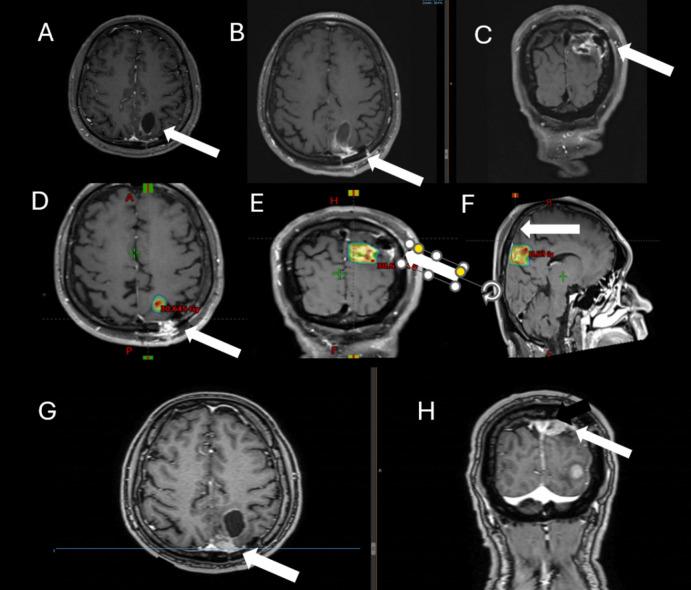

Breast cancer brain metastases (BCBM) are increasingly common due to improved systemic therapies prolonging survival. This study evaluates local control and factors influencing outcomes in patients with resected BCBM treated with postoperative stereotactic radiotherapy (SRT).

METHODS

A retrospective review included single resected BCBM treated with postoperative SRT from 2010 to 2022. The median follow-up was 28 months (range, 14-43). Variables analyzed included tumor size, biology, surgical corridor inclusion, radiation dose, and timing of SRT. Multivariable analysis was conducted using Cox regression.

62 patients were analyzed in multivariable analysis, HER2-positive status was associated with improved local control (HR: 0.76, 95% CI: 0.36-0.88, p = 0.032), as was a higher biologically effective dose (BED > 40 Gy, HR: 0.65, 95% CI: 0.45-0.89, p = 0.028). In contrast, tumor size > 5 cm (HR: 2.1, 95% CI: 1.7-4.6, p = 0.021) and delayed initiation of SRT beyond 28 days post-surgery (HR: 2.7, 95% CI: 1.9-4.7, p = 0.015) were associated with worse outcomes. Age, cystic metastases, inclusion of surgical corridor, and tumor location were not significantly related to local control. Radiation necrosis occurred in 13% of patients, predominantly asymptomatic.

由于全身治疗的改善延长了生存期,乳腺癌脑转移(BCBM)越来越常见。本研究评估了接受术后立体定向放射治疗(SRT)的切除性BCBM患者的局部控制情况及影响预后的因素。

一项回顾性研究纳入了2010年至2022年接受术后SRT治疗的单发切除性BCBM患者。中位随访时间为28个月(范围14 - 43个月)。分析的变量包括肿瘤大小、生物学特性、手术通道包含情况、放射剂量和SRT的时机。使用Cox回归进行多变量分析。

多变量分析纳入了62例患者,HER2阳性状态与更好的局部控制相关(风险比:0.76,95%置信区间:0.36 - 0.88,p = 0.032),更高的生物学有效剂量(BED > 40 Gy,风险比:0.65,95%置信区间:0.45 - 0.89,p = 0.028)也是如此。相比之下,肿瘤大小> 5 cm(风险比:2.1,95%置信区间:1.7 - 4.6,p = 0.021)以及术后28天以后延迟开始SRT(风险比:2.7,95%置信区间:1.9 - 4.7,p = 0.015)与更差的预后相关。年龄、囊性转移、手术通道包含情况和肿瘤位置与局部控制无显著相关性。13%的患者发生放射性坏死,主要为无症状性。